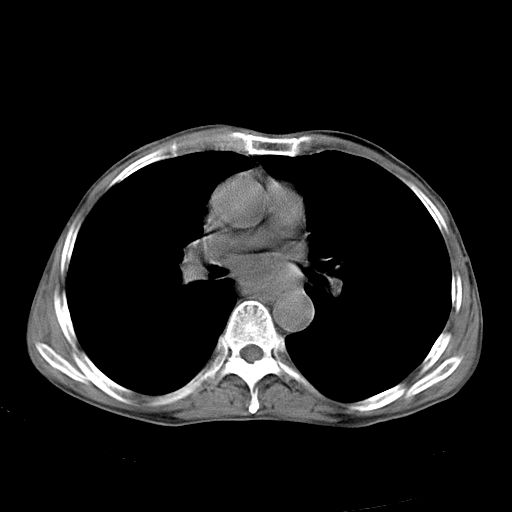

以下是引用苯小孩在2007-5-24 12:47:00的发言:[br]右侧肺门处不均匀密度软组织块影,远端肺组织见斑片模糊影,纵隔内淋巴结明显肿大,边界不清.<纵隔窗第12层面支气管内似见软组织结节>[br]考虑:1、右侧中央性肺癌并阻塞性肺炎并纵隔淋巴结转移可能性大.建议强化或纤支镜进一步检查.[br]2、隆突下淋巴结肿大/食道病变?请做鉴别检查.

以下是引用zhangzhongshou在2007-5-24 12:55:00的发言:[br]1、右肺中叶中心型肺癌并右肺门、隆突下、纵隔淋巴结转移。右肺中叶阻塞性肺炎。

以下是引用jw-830在2007-5-24 15:24:00的发言:[br][br] [br] 考虑右肺中央型肺癌并阻塞性炎症,右肺门及纵隔淋巴结转移。 [br] [br][br]